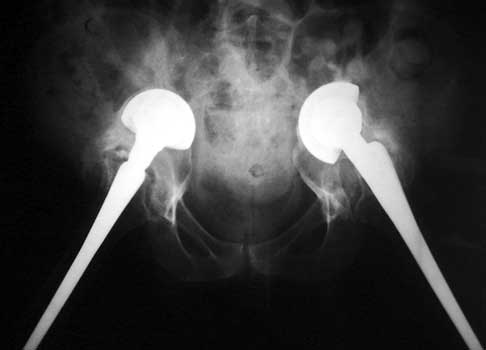

SUBSIDENCE - loose femoral prosthesis with interface widening,

osteolysis Gruen zone 6, cement fracture left femoral component

and osteolysis, with femoral component in valgus.